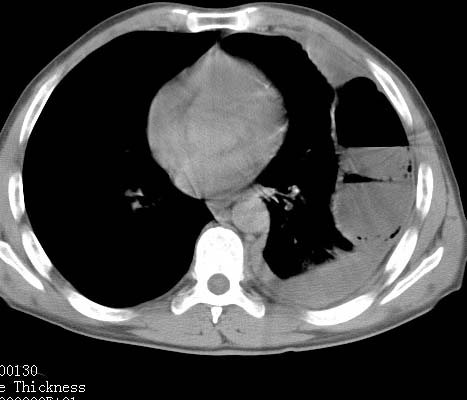

标题: CT10145:男性,30岁,活动后气促2月余.隔疝伴胸腔积液.右上肺结 [打印本页]

男性 病人 30岁,活动后气促2月余.隔疝伴胸腔积液.右上肺结核!

左侧胸腔积液,并胸腔内见多个含液 气组织,并相互重叠。影像特征很特殊,应该是“膈疝”。支持!

左侧膈疝,及左侧胸水,双上肺结核。

支持!左侧膈疝,左侧胸水,双上肺结核。